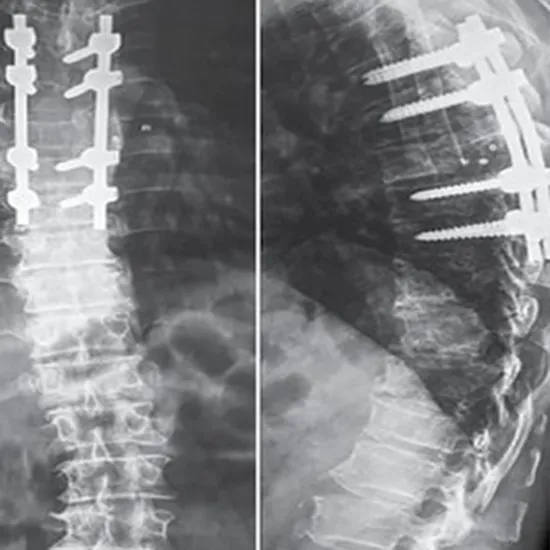

X-Ray Of The Thoracic Spine (AP/Lateral View)

The x-ray of the thoracic spine displays the twelve bones that run from the top and middle back area of the neck.

The x-ray of the thoracic spine aids in the evaluation of fractures in the twelve-bone structure. This x-ray is also taken if the patient feels numbness in their arm or hand. Accidents necessitate an x-ray of the individual's thoracic spine. This is to determine whether he has sustained internal injuries.